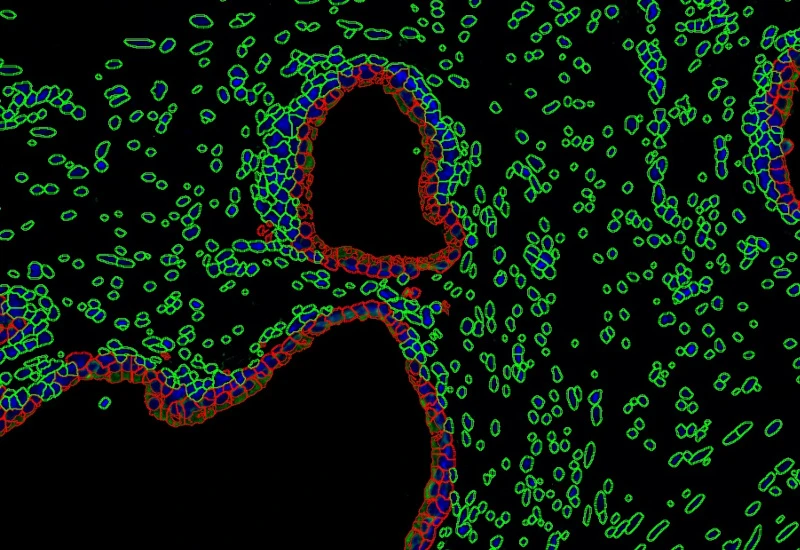

The Pulmo App segments nuclei and the metastructure components of the lung, including tissue, bronchioles, blood vessels, and alveoles. Each segmented metastructure is measured for up to 20 morphometric parameters.

App Category 3